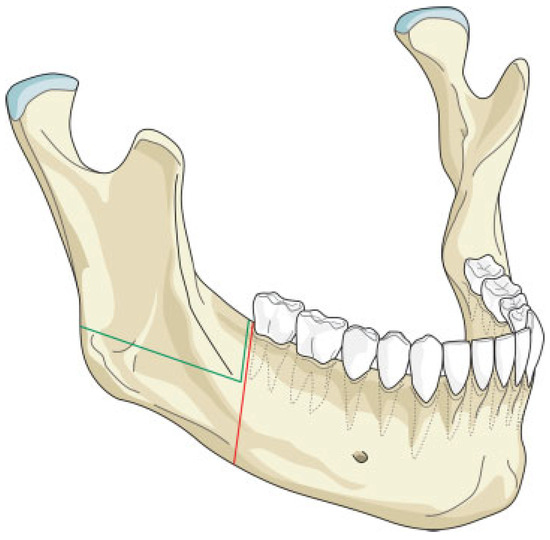

The mandibular resection is performed utilizing a horizontal osteotomy (Figure 1) above the mandibular angle on one side and a stepped body or angle osteotomy on the other side (Figure 2). A silicone template is created to the shape and dimension of the resected mandibular segment. The template is used as a guide to osteotomize the fibula at the donor site to reproduce the middle symphyseal segment of the mandible without shortening the fibula. The flap is then transferred to the recipient site and oriented so that one end will fit in the stepped osteotomy in a key and lock fashion (Figure 3) and the other end of the flap will overlap with the horizontal mandibular osteotomy (Figure 4), allowing room for adjustment in the anterior posterior direction to achieve the desired chin point projection (Figure 5). When the desired projection is achieved—guided by the silicone template—both ends of the flap are marked with a sterile pencil and trimmed using the saw; then miniplates are used to fix the flap in place (Figure 6).

Our technique is unique as it allows flexibility in adjusting the chin point projection to give the best possible aesthetic outcome. Trimming of the flap ends is performed at the recipient site to reduce the risk of short flap, but should this happen, the overlap at the horizontal osteotomy side will allow for compensation (Figure 4). Moreover, the greater surface contact area at the horizontal osteotomy side together with the key and lock fitting at the stepped osteotomy side (Figure 3) increase the stability of the flap and reduce the risk of rotation, hence allowing the use of miniplates for fixation; this in return allows room for placing more than one plate on each side, adding to the stability. The use of miniplates for fixation also facilitates the placement of implants in future rehabilitation.

Figure 1. Illustration of the horizontal osteotomy cuts (green lines). The red lines represent the conventional osteotomy cuts without the modification.